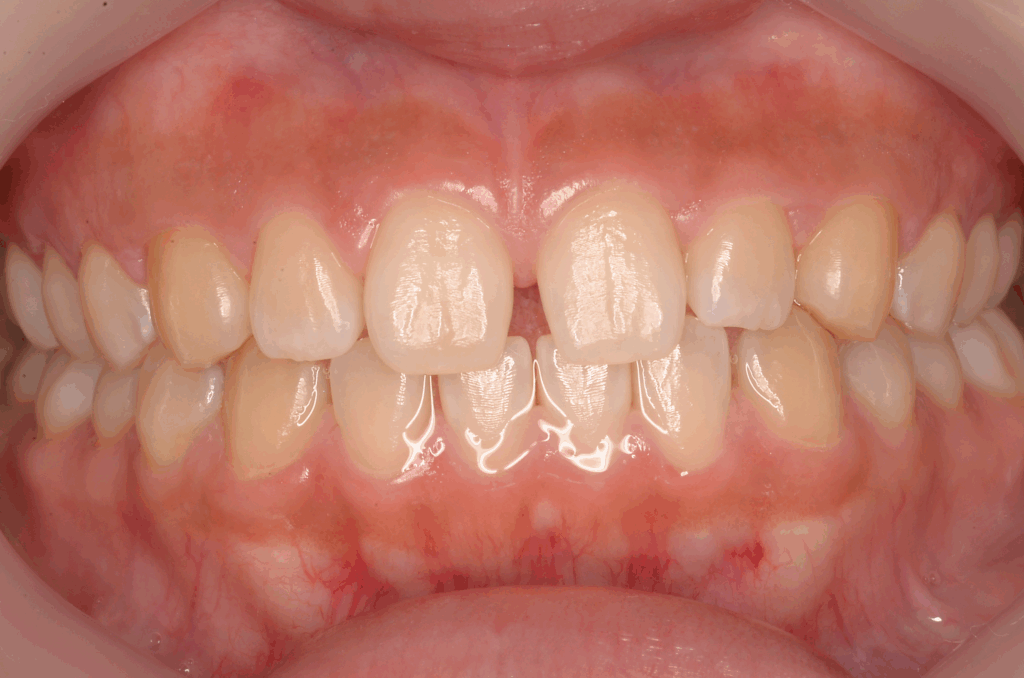

目立ちにくいマウスピースを使用した矯正治療も行っております。歯並びが気になっておられる方は一度ご相談ください。